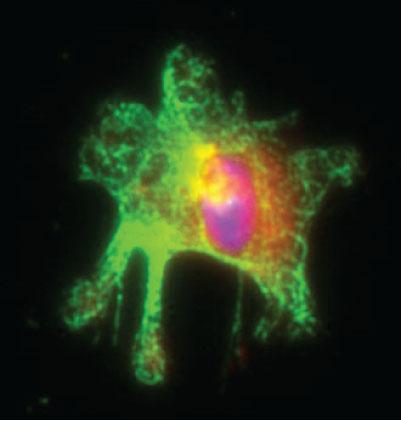

Activated Macrophage Isolated from Mouse Intestine (IMAGE)

Institute for Research in Biomedicine (IRB Barcelona)